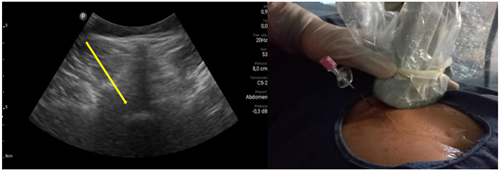

Los procedimientos fueron realizados en sala de operaciones, con vía venosa periférica y en posición decúbito ventral. Los mismos fueron realizados por el investigador principal (P. C.) con experiencia en la realización de procedimientos ecoguiados en la columna vertebral, utilizando la técnica paramediana en eje ecográfico corto. Se utilizó un ecógrafo portátil modelo Lumify marca Phillips, con transductor curvo de baja frecuencia. Fundas y gel ecográfico de la marca Pajunk® (Pajunk GmbH Medizintechnologie, Geisingen, Germany). En cada caso se identificó el espacio L4-L5 o L5-S1 mediante escaneo ecográfico de la columna lumbosacra en el plano transversal y longitudinal previo al inicio del procedimiento. Con la sonda ecográfica colocada en plano transversal o en eje corto, se realiza un habón anestésico 1 a 2 cm a un lado del transductor, correspondiente al lado del dolor radicular. La aguja de Tuohy ecogénica, 18 G (Tuohy Sono, 18G Pajunk® GmbH Medizintechnologie, Geisingen, Germany) de 9 o 12 cm según la contextura del paciente, se dirige en plano, en tiempo real, en sentido lateral a medial, entre la articulación facetaria por fuera y el ligamento interespinoso por dentro, hasta alcanzar el ligamento amarillo, en el espacio interlaminar elegido (Figura 1). El espacio epidural fue identificado mediante la pérdida de resistencia con suero fisiológico. Se registró la imagen doppler color durante la maniobra, como medida alternativa a la epidurografía con contraste (Figura 2). Posteriormente, 5 cc de contraste no iónico fue inyectado. Se consideró que fue alcanzado dicho espacio cuando el contraste se distribuye a lo largo del ligamento longitudinal posterior (Figura 2). 1 mg/kg de triamcinolona más 3 cc de lidocaína al 0,5 (hasta 10 cc de solución total) se inyectan en el espacio epidural.

Fig. 1. Escaneo ecográfico en eje corto o transversal del espacio L5-S1. La flecha amarilla muestra el punto de entrada de la aguja de Touhy en el abordaje paramedial y su trayecto. A la derecha se muestra la colocación de la aguja Sono Touhy en plano con el transductor curvo.